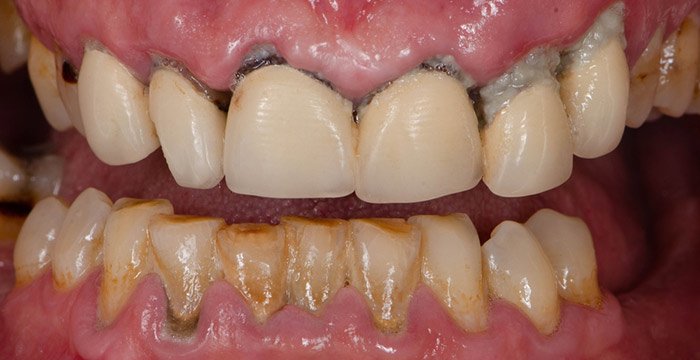

Периодонтит всегда начинается с воспаления десен, известного как гингивит. Одним из первых признаков является кровоточивость десен, когда вы чистите зубы. Десны могут выглядеть красными и опухшими, и вы можете заметить обесцвеченный слой бактериального налета на зубах. Если его не удалить путем надлежащей чистки зубов, этот налет станет «минерализованным», превратившись в твердые отложения, известные как зубной налёт или зубной камень, которые невозможно удалить зубной щеткой.

При отсутствии лечения гингивит может превратиться в периодонтит, более серьезную форму заболевания десен. Часто это происходит без каких-либо явных признаков, которые могли бы вас насторожить, но вы можете заметить такие изменения, как:

Повышенная кровоточивость десен, которая может быть спровоцирована чисткой зубов или приемом пищи, а может быть и спонтанной.

Неприятный запах изо рта.

Изменение положения зубов в челюстях.

Зубы кажутся «длиннее» (опущение десен).

Боль.

У курильщиков кровоточивость десен может быть менее заметной. Это связано с воздействием никотина на кровеносные сосуды и означает, что развитие болезни может быть скрытым.

Люди часто не замечают наличие периодонтита до тех пор, пока им не исполнится 40 или 50 лет, и к этому времени может быть нанесен значительный ущерб. Тем не менее, стоматолог может обнаружить признаки заболевания гораздо раньше, во время обычного стоматологического осмотра, и может контролировать состояние периодонта с помощью инструмента, называемого индексом пародонтального скрининга.